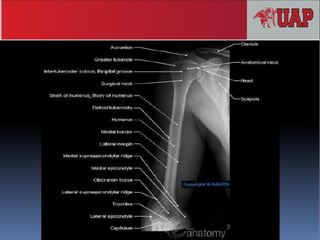

 Son huesos largos. Presenta 2 epífisis,

metáfisis y diáfisis.

 Epífisis proximal:

 Cabeza mueral

 Cuello anatómico

 Cuello quirúrgico (fractura con

mayor frecuencia)

 Troquín Tubérculo menor, lado

interno.

 Troquíter. Tubérculo mayor, lado

externo.

 Canal biscipital. Intertubercular.

 Epífisis distal:

 Cóndilo, epicondilo.

 Tróclea, epitróclea.

 Fosita coronoidea (anterior- interno)

 Fosita radial (anterior – externo)

 Fosa olecraneana (posterior-

inseción del radio)

 Diáfisis:

 Impresión deltoidea

 Canal de torsión o radial

Epicóndilo

HÚMERO